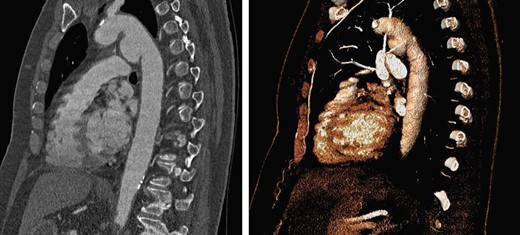

A 74-year-old woman was referred to our vascular service with a 6-month history of hoarseness of voice and intermittent dry cough. The patient’s medical history included hypertension and gastroesophageal reflux disease. Flexible laryngoscopy demonstrated a foreshortened, lateralised and flaccid vocal fold consistent with unilateral vocal cord paralysis. Subsequent computed tomography (CT) imaging of the neck and thorax revealed a saccular aneurysm in the aortopulmonary window measuring 39 mm (Fig. 1). Digital subtraction angiography confirmed the presence of a ductal aneurysm with a well-defined neck and no intraluminal thrombus (Fig. 2). There was no contrast extravasation into the mediastinum or pulmonary circulation. Following a cardiovascular multidisciplinary meeting, treatment options were discussed with the patient and consensus favoured endovascular repair. The distance from the proximal margin of the aneurysmal neck to the origin of the left subclavian artery measured just under 2 cm and therefore did not meet the manufacturer’s minimal landing zone requirements. To circumnavigate this dilemma, a left subclavian stent graft was inserted with its proximal end parallel to the main thoracic endoprosthesis. The procedure was uncomplicated and repeat imaging revealed widely patent stent grafts with satisfactory positioning and absence of endoleak (Fig. 3). Our patient was discharged home on the second postoperative day. She continued speech and language therapy postoperatively and has made remarkable recovery of phonation, declining any further treatment options for same.

Sagittal CT with 3D reconstruction demonstrated a 39-mm saccular aneurysm along the lesser curvature of the aortic arch, expanding in the direction of the pulmonary artery.